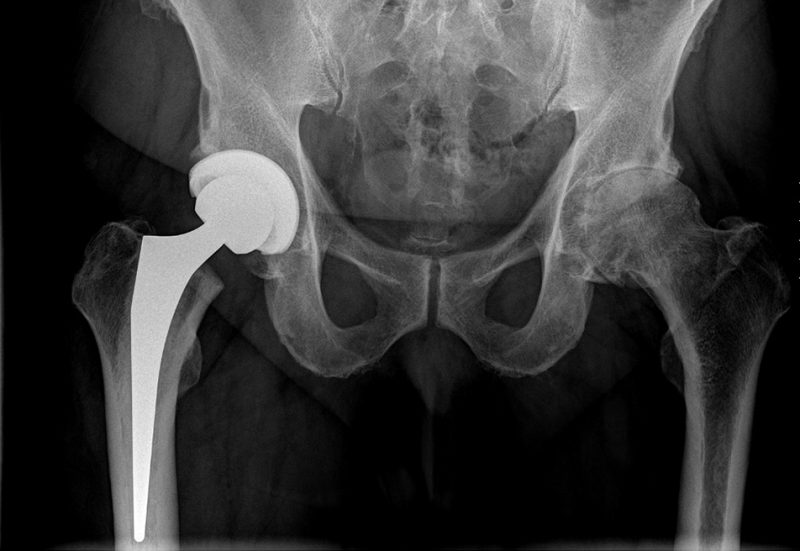

In unserer Abteilung werden primäre und Revisionsendoprothesen an Hüft –, Knie – und Schultergelenken durchgeführt.